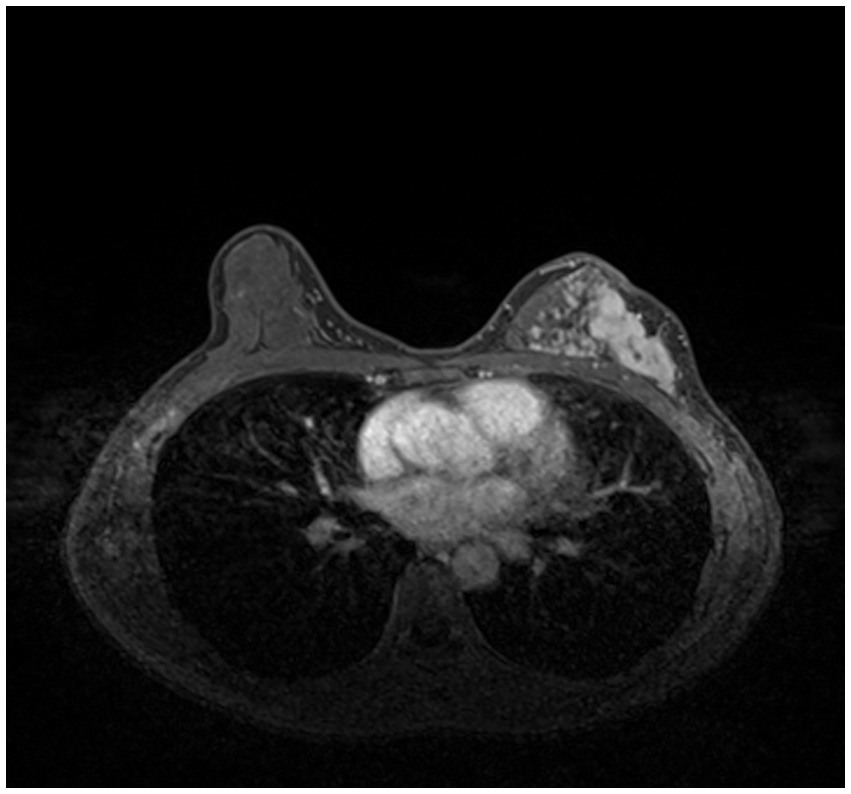

Compared with other types of medical imaging technologies, such as Computed Tomography (CT) and Positron Emission Tomography (PET), MRI provides better imaging capability for soft tissues and is widely adopted in breast cancer diagnosis and treatment. In our work, we use Dynamic Contrast-enhanced Magnetic Resonance Imaging (DCE-MRI), which provides a high-quality image for soft tissues with better quality of blood flow around the lesion, which facilitates higher accuracy and earlier detection in breast cancer diagnosis. Despite the above, due to the nature of medical imaging technology, a common DCE-MRI image for breast cancer diagnosis (Figure 1A), contains a large amount of redundant information, so we need to extract only the lesion region of interest for further processing in order to achieve better performance. Image segmentation is widely used in medical imaging analysis, where pixels from specific regions are segmented from the background. With the prevalence of deep learning, models such as the Fully Convolutional Network (FCN) (9) and UNet (10) are applied in medical image segmentation and achieve great performance. It is also proven that neural networks are effective and efficient in breast tumor segmentation tasks (11). In our work, considering the fact that breast cancer lesions are close to the chest wall and vary in size and distribution, we propose a two-step lesion segmentation method using nnUNet (12) as shown in Figure 1: (1) segmentation of the mammary gland region; (2) segmentation of the breast cancer lesion region within the mammary gland region. When training medical image segmentation models, transferability should be taken into consideration because DCE-MRI images collected from different centers may vary in resolution, scanner used, protocol, and image quality. Hence, we apply a histogram matching method (13) to augment the training samples in order to improve the model transferability.

Figure 1

The proposed two-step breast cancer lesion segmentation method. (A) is a DCE-MRI image sample for breast cancer diagnosis, which contains irrelevant regions, such as the heart; (B) shows the segmented mammary gland region in red; (C) shows the breast cancer lesion region in red.

As introduced in Section 1, and referring to Figure 1A, a common DCE-MRI image for breast cancer diagnosis contains a large amount of information that is irrelevant, so we needed to extract only the concerned lesion region for later processing in order to achieve better performance. Another notable reason for breast cancer lesion segmentation is that there is similar imaging intensity in the heart region in DCE-MRI images, as shown in Figure 2, so it is preferable to remove the heart region in order to reduce the probability of false positives. In the following, we elaborated on the proposed two-step lesion segmentation method to extract breast cancer lesion regions based on nnUNet and introduced a simple histogram matching method to augment the training samples in order to improve the model transferability between different centers.

Figure 2

Two red rectangles show similar imaging intensity in the breast and heart regions.

3.1.2 Two-step lesion segmentation

In order to reduce the probability of false positives, we utilized a two-step lesion segmentation method to extract the breast cancer lesion region. As shown in Figure 1, given a DCE-MRI sample for breast cancer diagnosis, we first segmented the mammary gland region, based on which we then segmented the breast cancer lesion region.